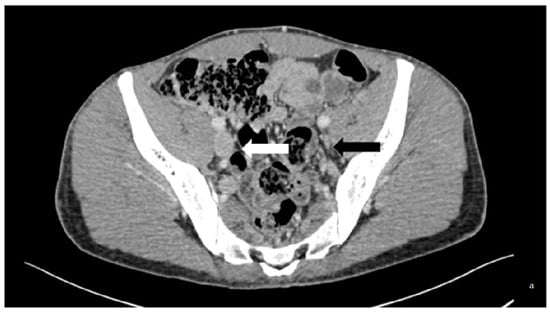

Figure 1.

Case of a 33-year-old patient with thrombophilic disease whose first DVT was diagnosed in 2013. He displayed PTS. (a) is a transversal slice of a CT scanner that shows the baseline phleboscanner with a collapsed left external iliac vein (black arrow) compared to the collateral one (white arrow) confirmed on (b), which shows phlebography assessment in a posterior incidence (black arrow). The treatment consisted of an angioplasty/stenting of the iliofemoral vein by popliteal vein approach, the results of which are displayed on the digital subtraction angiography (c).